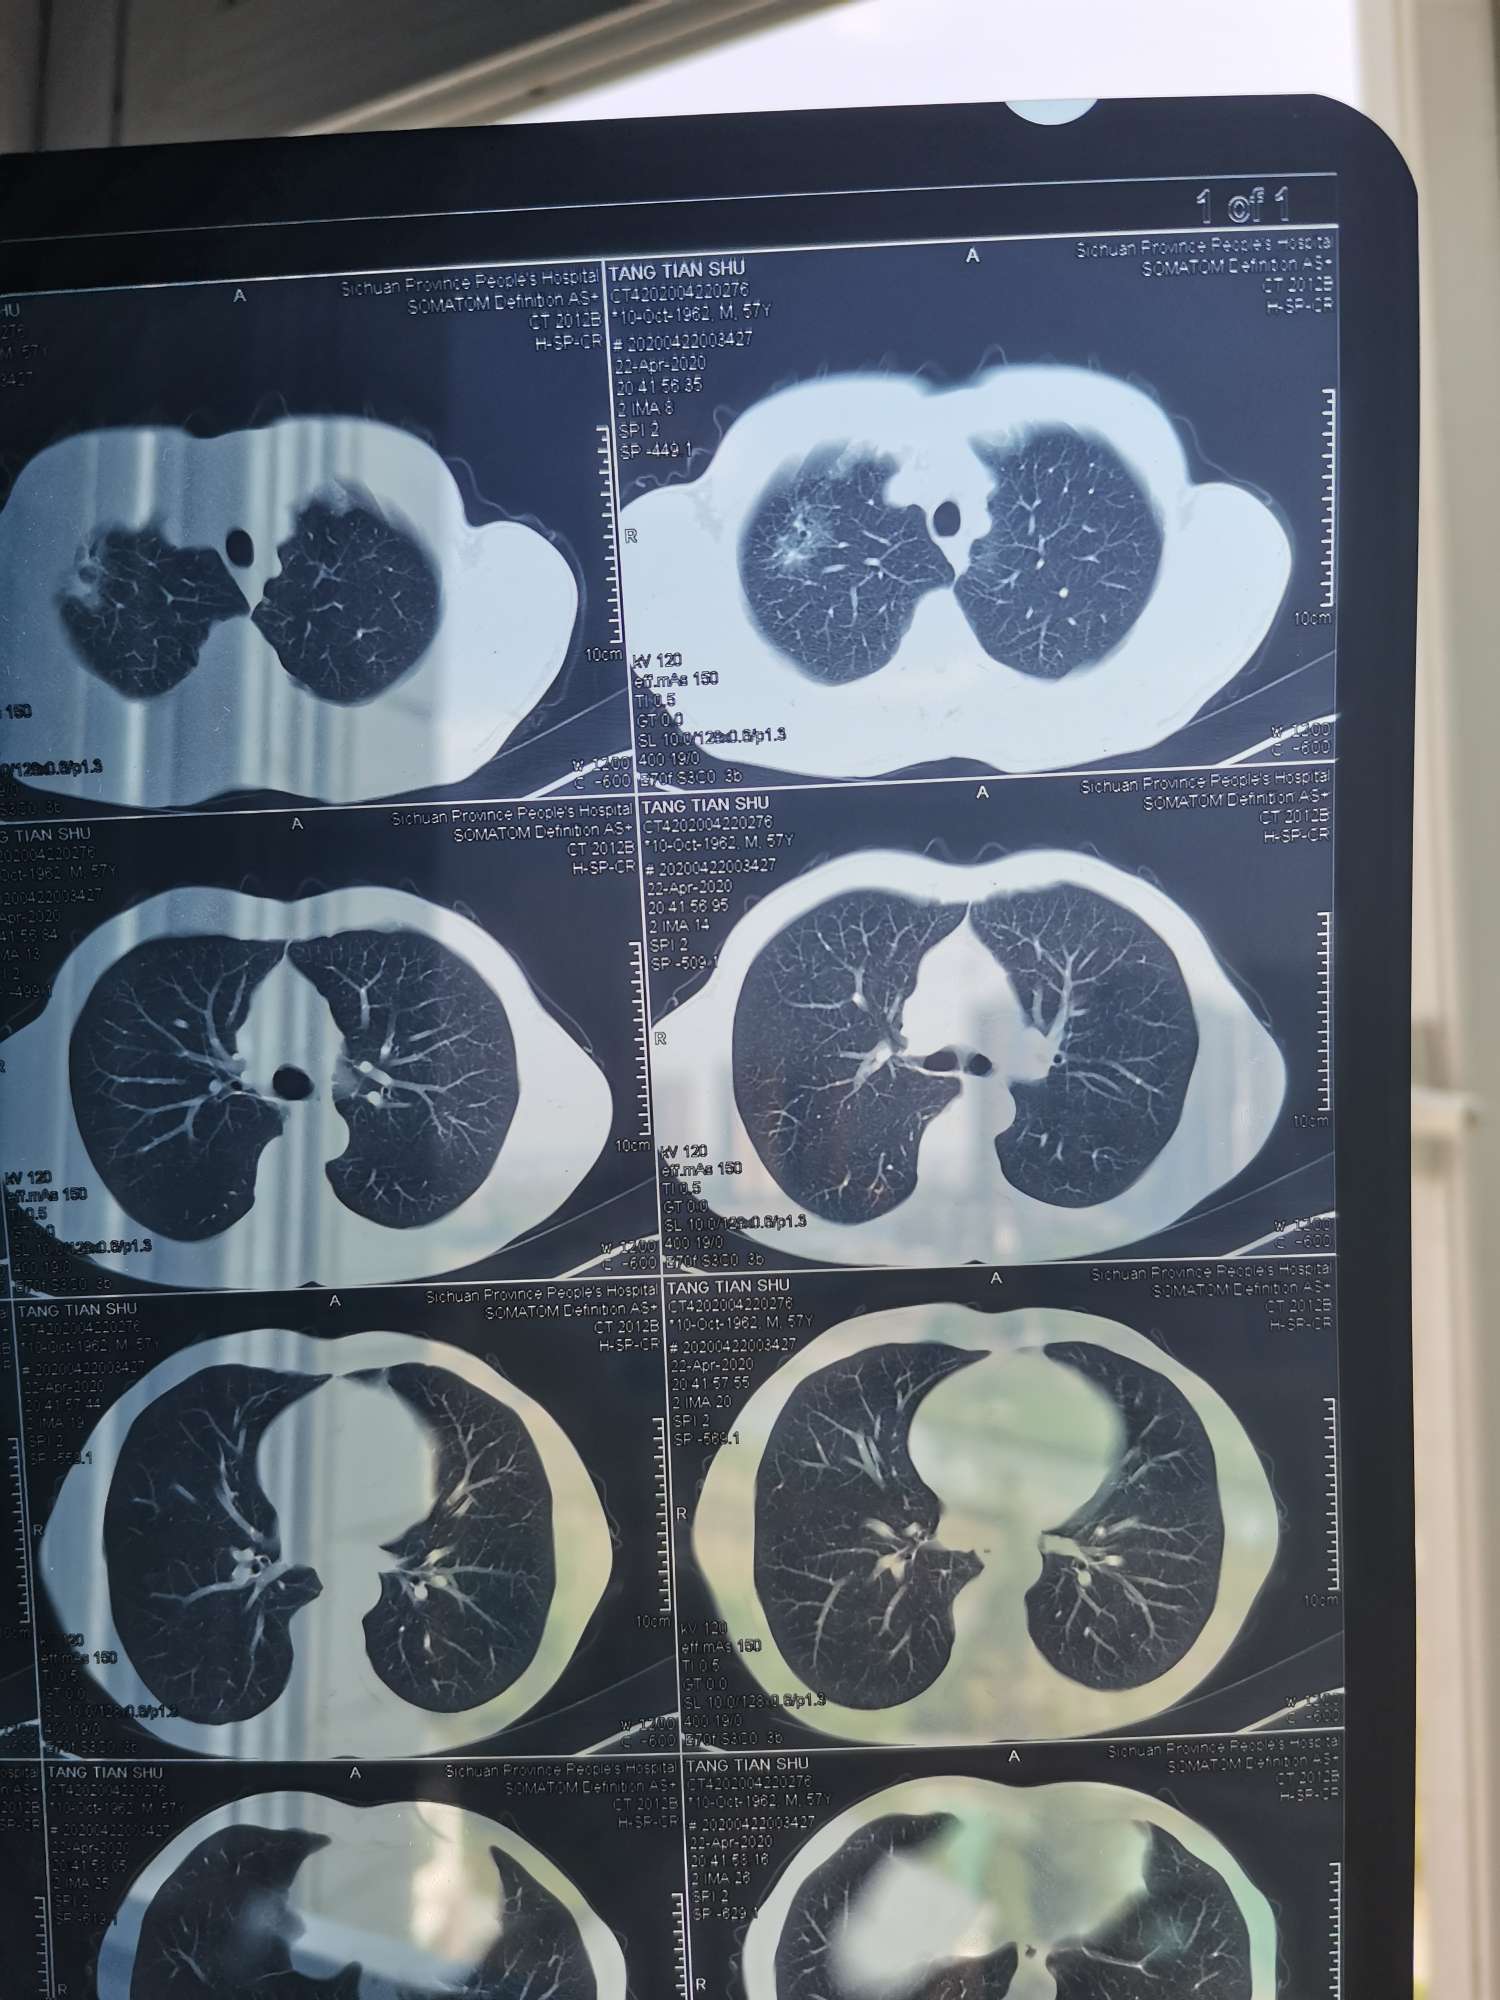

是否为腺癌,影像上不好判断,病理诊断为金标准,单从报告单上看,还不严重,可能有手术的机会

看ct结果没有转移,能做手术就尽快手术,一次性切除病灶!后期采用化疗和靶向治疗防止复发,以后定期复查不用担心太多!

是不是癌标准是取组织病理确诊,另外可查血肿瘤指标超出正常范围的话癌的可能性大,早期未转移手术是最佳选择,判断有无远端转移可以pet-ct。

是不是恶性肿瘤需要完善检查,才能定性。而且癌种不能通过影像确定,需要病理检验才能确定

请大家看看这个是不是肺腺癌?如果是的话分期严不严重分期